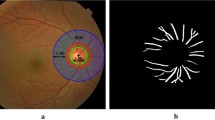

The investigation of artery vein changes over time is considered to be the significant diagnosis process of retinal diseases like diabetic retinopathy. The diagnosis includes the characteristics analysis of artery vein vessels, changes in its tortuosity level and artery vein ratio; hence, it is important to classify the artery and vein in a better way. Computer-aided diagnosis requires the automated classification of retinal artery and vein for diagnosing the progression of diseases. In this paper, a supervised classification with Bat algorithm is proposed to discriminate the artery and vein vessels in the retinal fundus images. A novel feature vector space, including both additive colour space as well as luminous chromaticity model colour space, is constructed. BAT algorithm is applied to select the feature group which improve the classification accuracy and also to reduce the dimensionality of feature space. The proposed method is developed and analyzed using the publicly available databases DRIVE, IOSTAR and STARE.